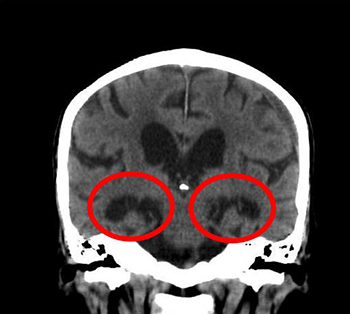

CT検査はエックス線を使って身体の断面を撮影する検査です。 当院では16列CT装置を設置しており、検査時間もわず2~3分(頭部CT)寝て頂くだけです。頭部(脳)のCT検査では、脳の形を見る事で、脳萎縮の程度を調べます。 脳全体と、記憶を司る側頭葉内の海馬の萎縮が確認されると、アルツハイマー型認知症の疑いがあります。